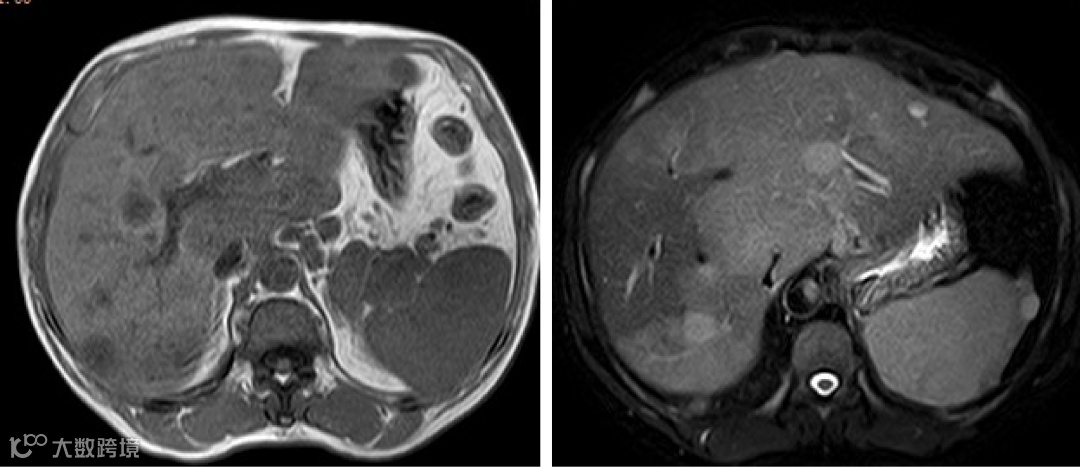

肝门区、胃小弯侧、腹膜后、腹主动脉旁多发淋巴结,部分肿大、融合,肝内多个弱强化结节,脾脏弱强化灶

肝内见多发片状、结节状长T1稍长/长T2异常信号影,DWI高信号